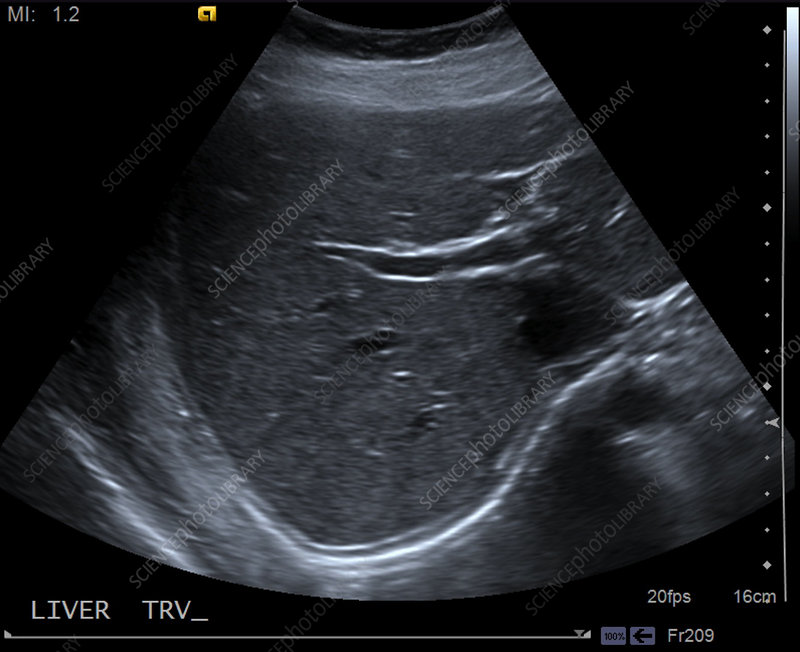

ultrasound scans including vascular Doppler and Musculoskeletal scans

At Wollondilly Radiology, we combine cutting-edge technology with clinical expertise to provide a comprehensive range of ultrasound services tailored to your health needs. We specialize in Vascular Doppler imaging to precisely evaluate blood flow and detect circulatory conditions like DVT or arterial blockages, alongside Musculoskeletal (MSK) scans designed to diagnose joint, muscle, and tendon injuries with high-resolution clarity. Whether you require routine screenings or specialized diagnostic assessments, our commitment to precision ensures you receive the most accurate results for your peace of mind and continued care.

Shearwave Elastography – Liver

-

Booking & Preparation

-

Expert Imaging & Care

-

Quality Clinical Analysis

-

Seamless Results Delivery

Shearwave Elastography – Liver

When a physical exam or a standard ultrasound reveals a nodule or liver concern, the next step is often a painful needle biopsy. Shearwave Elastography…

Shearwave Elastography – Liver